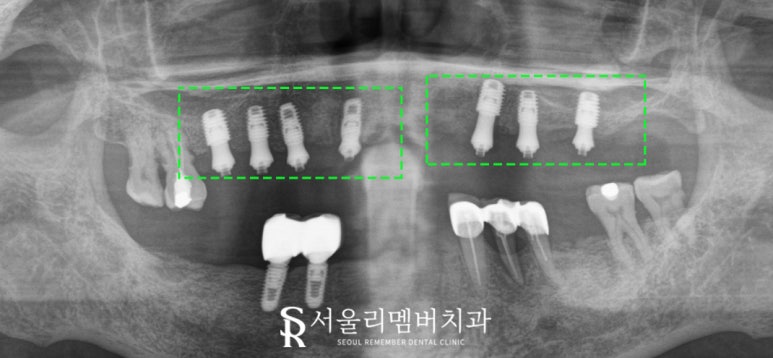

상악동과의 거리를 꼼꼼히 확인한 다음

환자에게 맞는 픽스처를 심어드렸습니다.

앞에서 언급했듯이 위쪽은 아래로 내려오는 힘이 전달되기에

아래쪽에 비해 제대로 된 고정력을 얻지 못할 확률이 큰데요.

따라서 좀 더 굵고 직경이 큰 픽스처를 사용하여

안정된 고정력을 얻을 수 있도록 유도했습니다.

잠깐! 픽스처를 심었지만 크라운은 올라가지 않았죠?

보통은 임시 치아 형태를 올려드리는 반면,

서울대입구역 치과 에서는 MUA(multi unit abutment)를 이용해

부착형 임시치아를 장착해 드렸습니다.

이게 뭐지? 궁금해하실 텐데요.

이가 하나도 남아있지 않은 무치악 환자에게 사용되는 것으로

이중 지대주가 있기 때문에 보다 안정적인 결과를 얻을 수 있죠.

임시 보철을 통해 교합 조정과 잇몸 회복을 마친 뒤에

지르코니아로 제작된 크라운을 올려드리기로 했습니다.